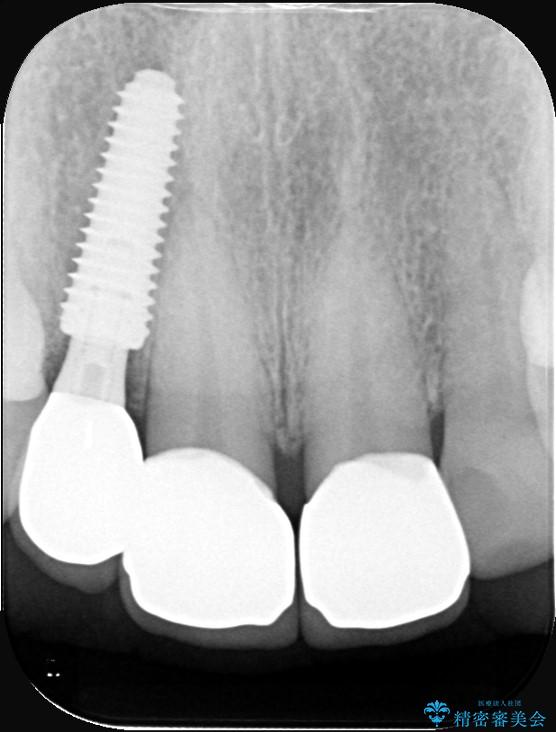

インプラント治療は、低侵襲で短期間に行える「抜歯即時インプラント治療」を選択しました。

この方法は、抜歯したその日にインプラントを埋入し、手術が1回で済むのが大きな特徴です。

治療期間も短く、抜歯からわずか3か月でオールセラミッククラウンを装着することができます。

また、オペ当日には仮歯まで装着するため、見た目を気にせず普段通りの生活を送ることができます。